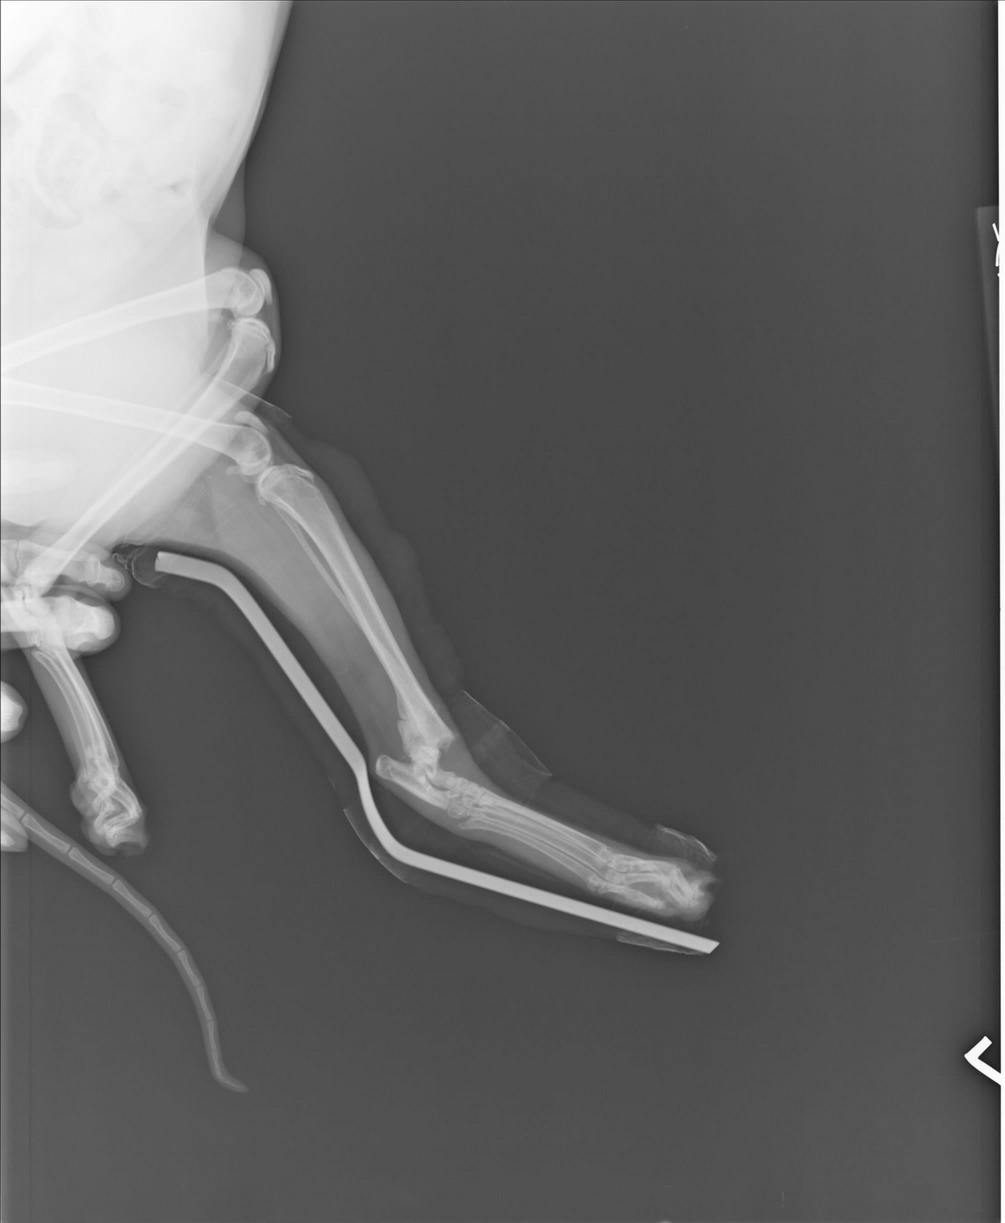

2周後聽其他喵友意見再帶去愛達司再照一次X光(圖2),醫生表示斷骨處已開始修復,無需再動手術,用鋁板固定包紮後一樣帶回家關籠靜養。2周後4/3回診再照一次片子(圖4),骨頭長的還不錯就拆掉鋁板,但一樣關籠讓喵開始習慣用左腳。目前仍在我家觀察左腳復元情況。